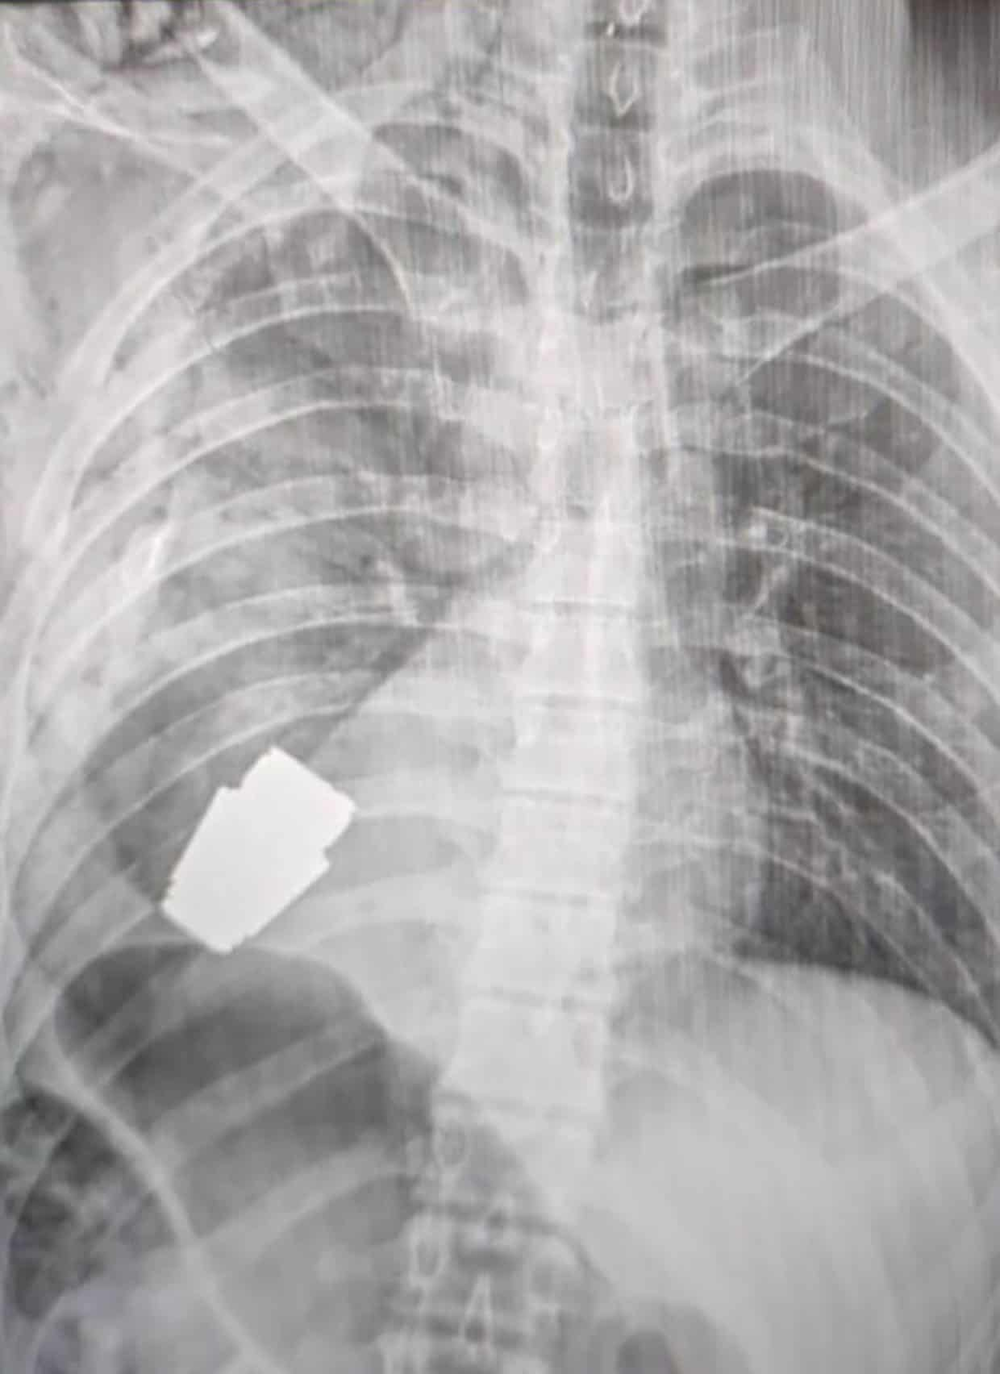

8. 医生从士兵心脏下成功“拆除”一颗手榴弹

一场足以载入教科书的医学奇迹在乌克兰发生。

首先,病人能被送上手术台就是幸运之神的眷顾。在俄乌冲突的战场上,一名士兵心脏下方嵌入了一颗手榴弹,它恰好没有伤及心脏,而且恰好没有爆炸。

军医看到片子时,整个人都惊呆了,他从没处理过这样棘手的案例。

“手榴弹没有爆炸,但仍然具有爆炸性。”

因此军医在手术过程中不能使用电凝术——这是手术中控制出血的常用方法——而且必须由两名懂拆弹的工兵全程陪同。

经过令人头皮发麻的紧张手术,手榴弹被成功取出,并解除爆炸可能,伤者病情稳定。

军医大概也没想到,有一天自己还会担任拆弹的重任。